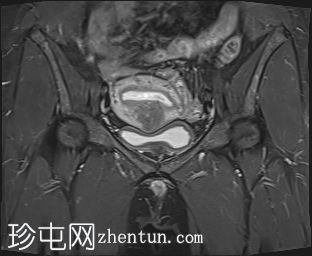

矢状位

T2加权像

增大的子宫腹股沟区(AVF)显示:

子宫前壁交界区局灶性增厚,边界不清。形成直径约3厘米的局灶性肿块样病变,轻度压迫膀胱。肿块边界模糊不清,可见多个细小出血灶,在T1加权像和T2加权像上均呈高信号,提示局灶性子宫腺肌症。

子宫体前壁可见另一处病灶,位于上述病灶尾侧,边界清晰(有包膜)。该病灶在T1和T2加权像上均呈低信号,内部未见异常信号灶,周围可见少量明显血管通道,提示为小型子宫肌瘤。

子宫内膜厚度正常。

宫颈MRI表现正常,可见少量纳博氏囊肿。

边界模糊不清是局灶性子宫腺肌症(无包膜)的特征。此外,病灶内存在多个微小的内部出血灶(异位腺体),且邻近增厚模糊的交界区,这些都是局灶性子宫腺肌症的诊断标准。

在上述病灶尾侧可见另一处具有不同影像学特征的病灶,该病灶边界清晰(有包膜),且信号均匀(无微小的内部出血灶),提示可能合并子宫肌瘤。